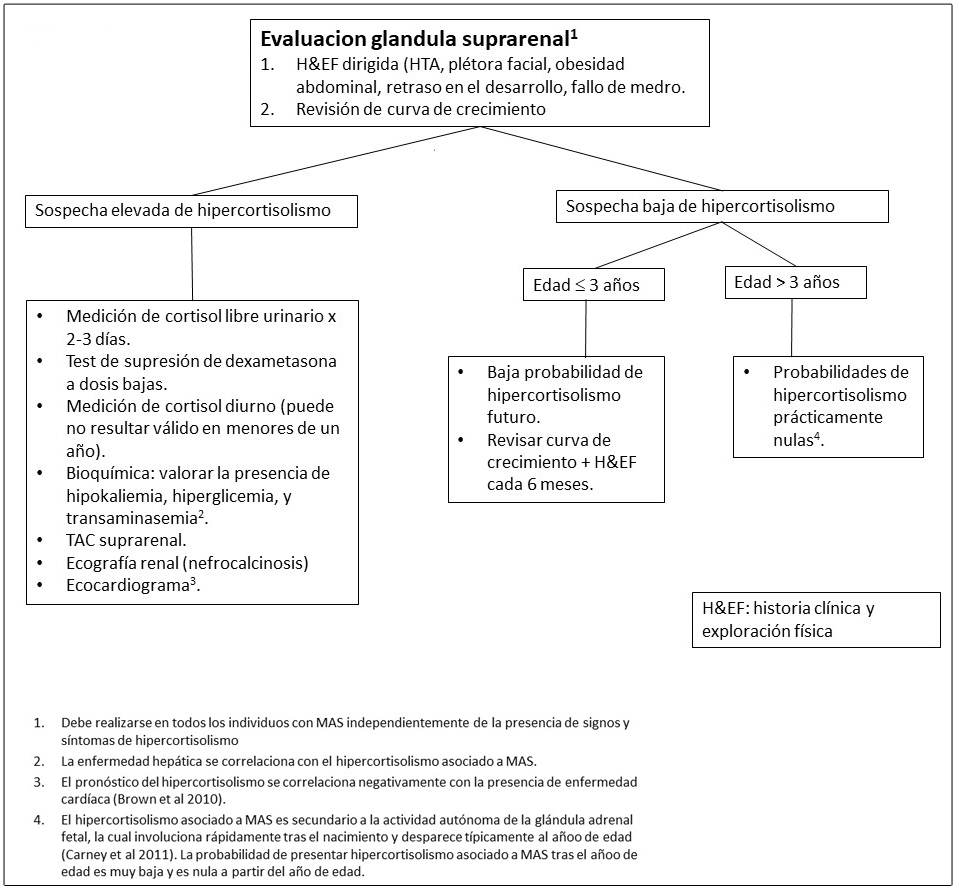

Hipercortisolismo.

En raras ocasiones, los bebés con DF/MAS pueden debutar con un síndrome de Cushing secundario a un exceso de producción de cortisol por la glándula adrenal fetal (Brown et al 2010, Carney et al 2011). Los síntomas suelen desarrollarse durante el periodo neonatal y pueden llegar a ser muy graves resultando incluso en la muerte. La regresión espontánea de este síndrome de Cushing se ha reportado en aproximadamente la mitad de los supervivientes, presuntamente secundaria a la involución de la glándula fetal adrenal.

Figura 9. Evaluaciones recomendadas para la disfunción de las glándulas suprarenales en individuos con Displasia Fibrosa/Síndrome de McCune-Albright